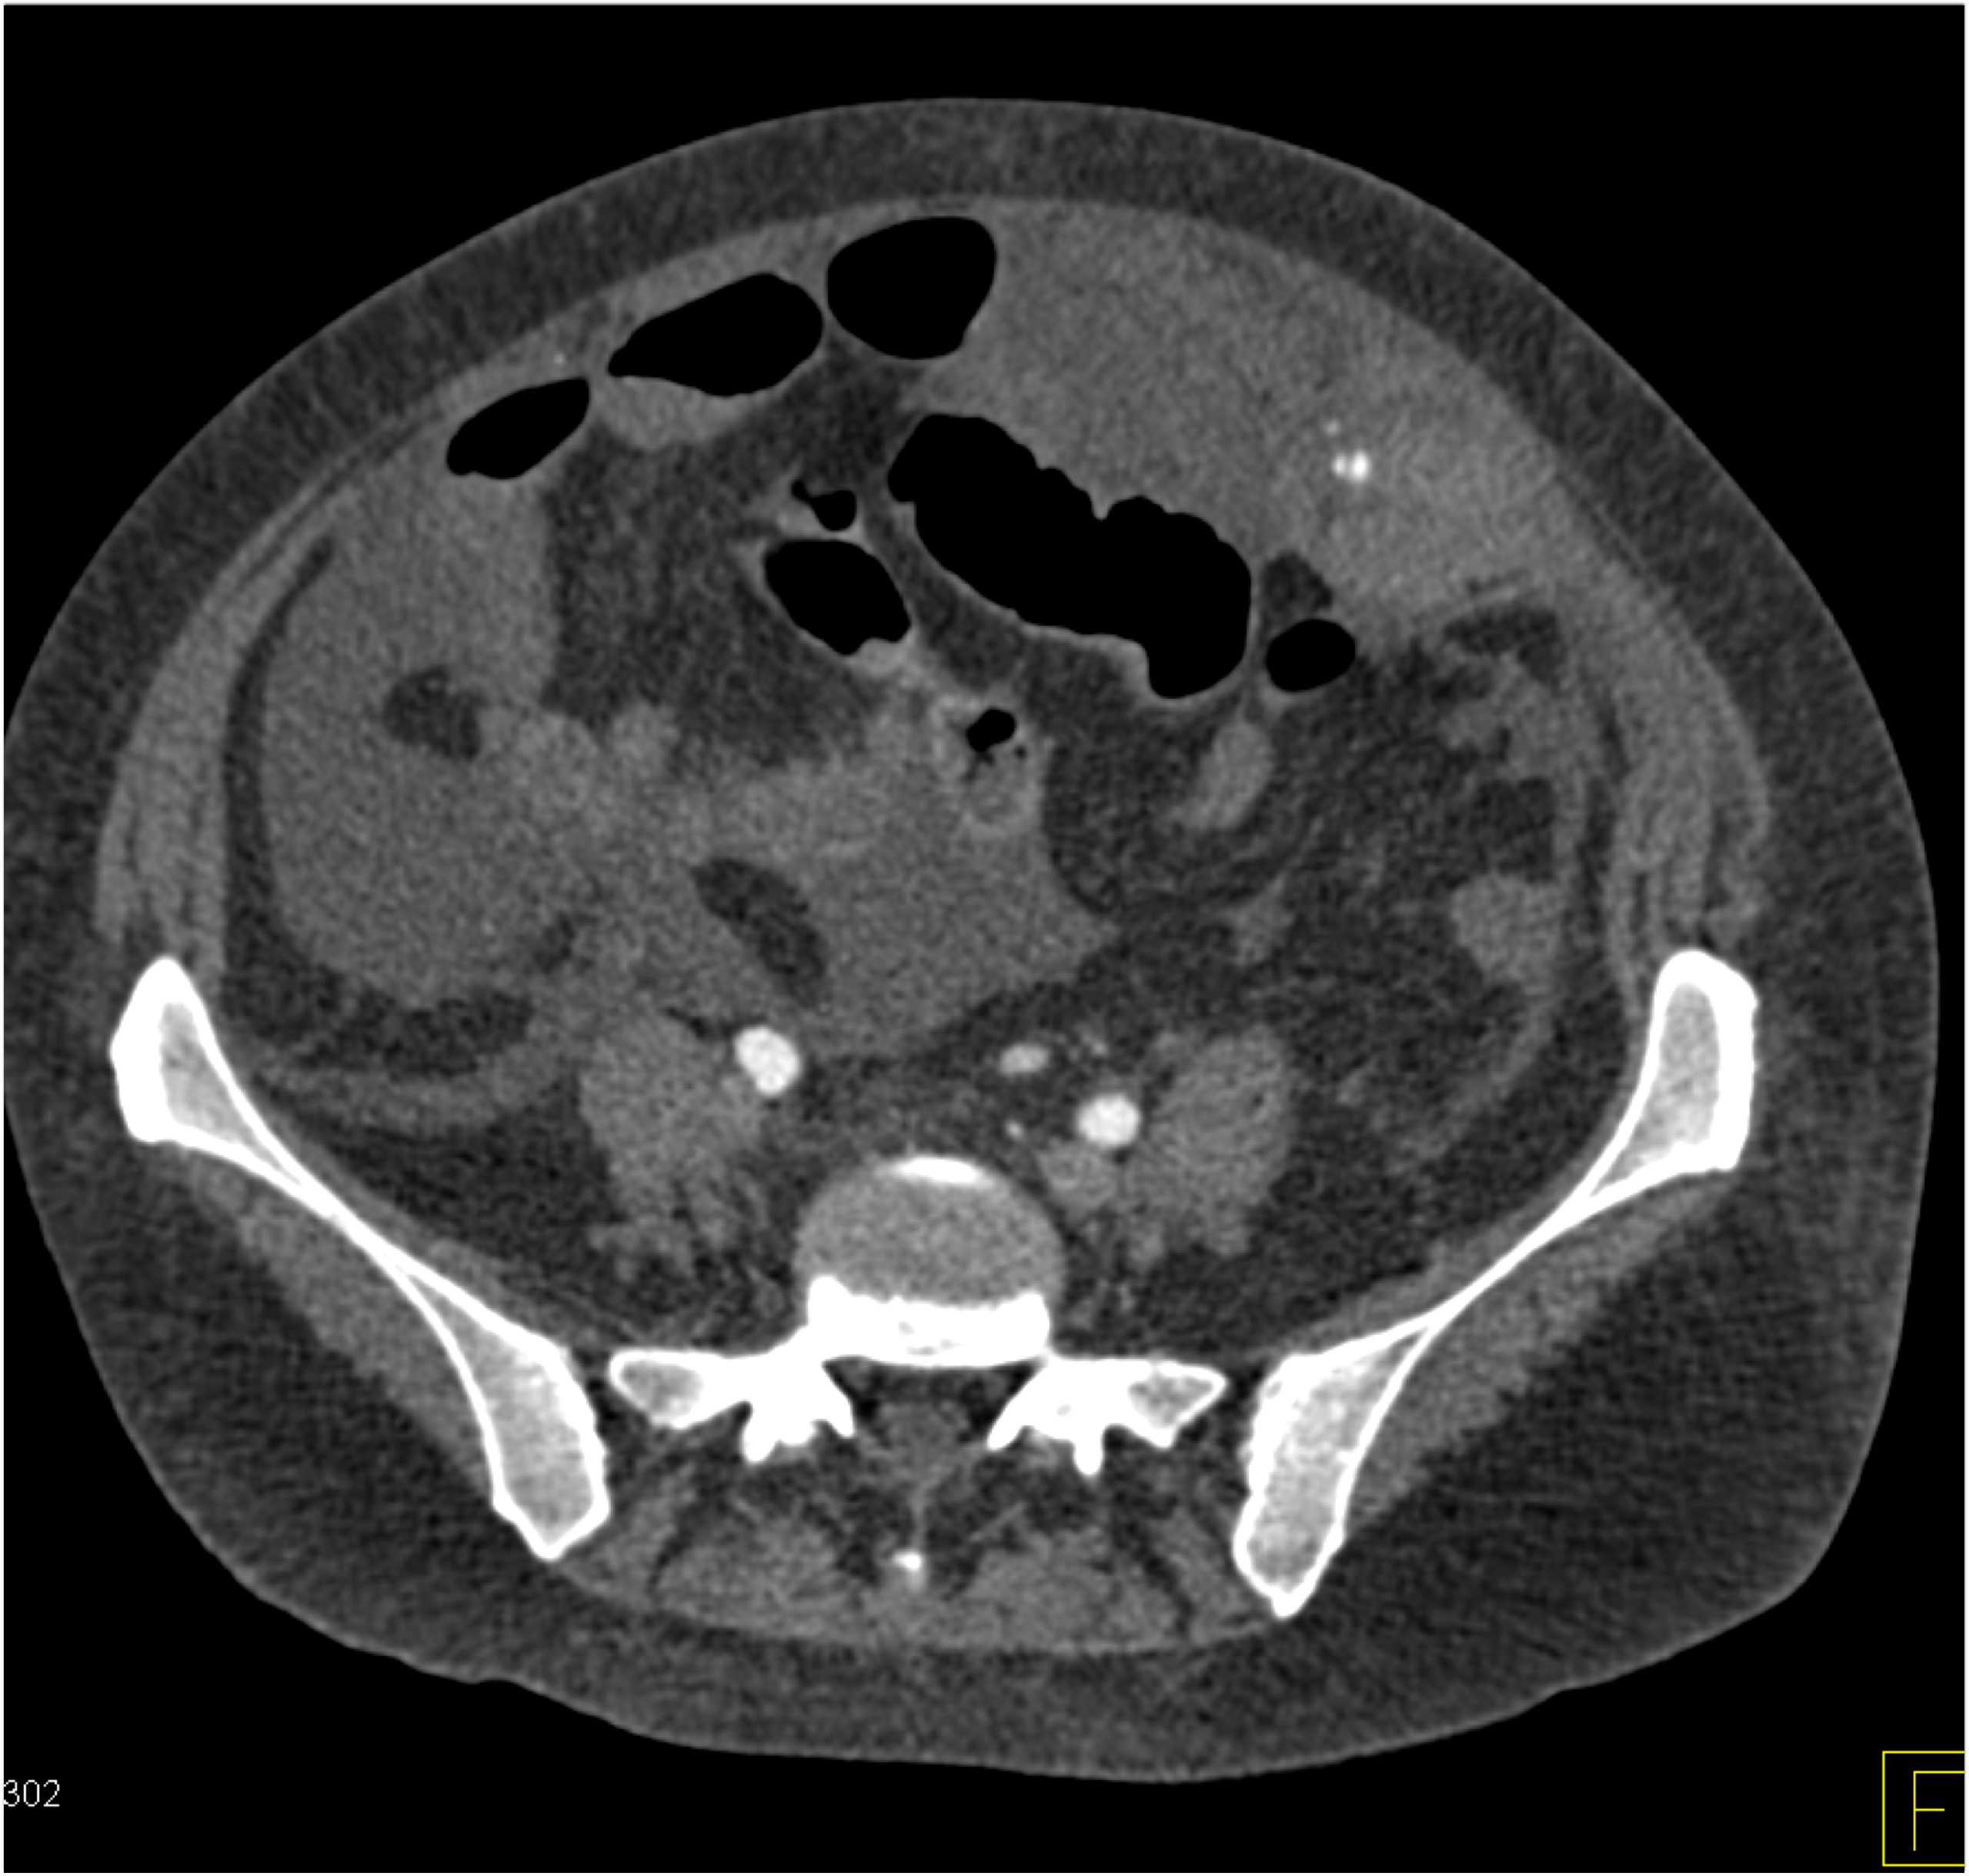

9) The best diagnosis in this 30ish year old female is?

renal cell carcinoma

MEST tumor (mixed epithelial and stromal tumor)

Wilms tumor

polycystic kidney disease